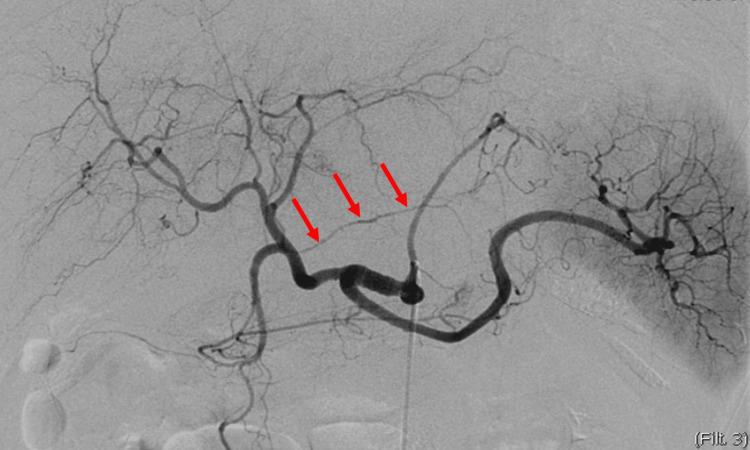

Gastric artery injury resulting from blunt abdominal trauma is rare, with only eight previous cases documented in the published literature. Our report describes a case involving an injury to the right gastric artery with concomitant injuries to the liver and spleen, for which arterial embolization targeting the right gastric artery was performed. The patient, a 66-year-old woman without any remarkable medical history, was involved in a motor vehicle accident. She was brought to the hospital in a state of shock and complaining of upper abdominal pain. Contrast-enhanced CT indicated hepatic and splenic injuries, intra-abdominal hemorrhaging, and effusion of contrast medium, suggesting involvement of the right gastric artery. Subsequent angiography confirmed irregularities in the diameter of the right gastric artery, prompting coil embolization. A conservative therapeutic approach was selected due to the absence of evidence regarding active hemorrhage or vascular injury within the hepatic or splenic regions. The patient remained clinically stable following the embolization, without any sequelae. Arterial embolization is warranted if preoperative contrast CT indicates signs of hemorrhage, even if hemostasis is ostensibly attained during angiography. Our findings allude to the feasibility of non-operative management (NOM) rather than laparotomy for cases of gastric artery injury.

钝性腹部创伤导致的胃动脉损伤较为罕见,既往发表的文献中仅记录了8例。我们的报告描述了1例涉及右胃动脉损伤并伴有肝脾损伤的病例,针对该病例对右胃动脉进行了动脉栓塞治疗。患者为一名66岁女性,无任何显著病史,遭遇了机动车事故。她被送至医院时处于休克状态,主诉上腹部疼痛。增强CT显示肝脾损伤、腹腔内出血以及造影剂渗出,提示右胃动脉受累。随后的血管造影证实右胃动脉直径不规则,遂进行弹簧圈栓塞。由于没有证据表明肝脾区域存在活动性出血或血管损伤,选择了保守治疗方法。栓塞术后患者临床情况稳定,无任何后遗症。如果术前增强CT显示出血迹象,即使在血管造影时表面上已实现止血,也有必要进行动脉栓塞。我们的研究结果表明,对于胃动脉损伤病例,非手术治疗(NOM)而非剖腹手术是可行的。